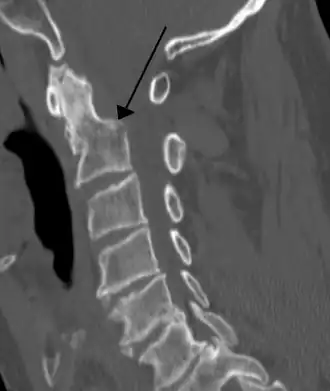

Na tomografia computadorizada ou radiografia, uma fratura cervical pode ser visualizada diretamente. Além disso, sinais indiretos de lesão pela coluna vertebral são incongruências das linhas vertebrais,[6] e/ou aumento da espessura do espaço pré-vertebral:[7]